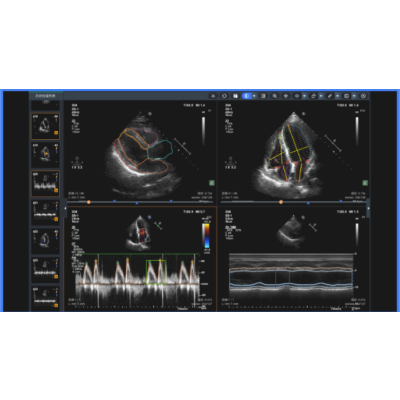

本软件利用AI技术可以自动识别超声心动图的标准切面,自动测量心脏和大血管的结构和功能参数,极大提高医生处置效率;自动测量多种心功能常规参数。

本软件采用独家动态影像处理技术+4D-flow+神经网络仿生机制+注意力机制,分别采用3万+心脏超声数据用于模型训练,重点模型算法有切面质量评估、切面分类模型、切面重点区域分割、心动周期识别切面、频谱波形轮廓和关键点识别模型和算法组成。